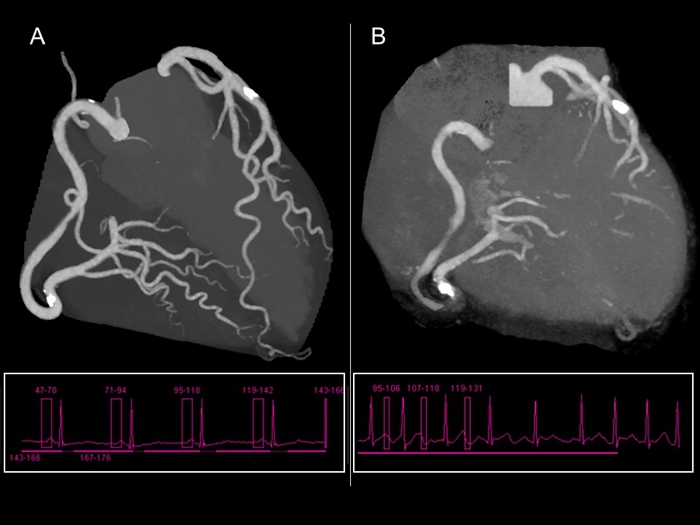

不整脈

A: 洞調律時に撮影. B: 心房細動時に撮影

不整脈も冠動脈CTの画質低下の要因の1つです。 AとBはいずれも同じ人の冠動脈CT画像ですが,

Bの心房細動時の撮影では画質が低下しています。